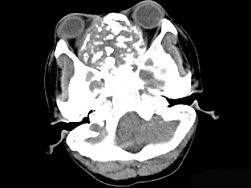

男性,28岁,因鼻塞、头痛1年余,鼻窦CT扫描如图所示,请选择正确的描述与结论()

A.双侧上颌窦、筛窦、鼻腔及蝶窦内见软组织肿块影

B.肿块内密度不均,有较多致密钙化影

C.窦壁及颅底骨质破坏

D.考虑鼻窦骨瘤

E.考虑为鼻窦软骨瘤

[多选题]男性,28岁,因鼻塞、头痛1年余,鼻窦CT扫描如图所示,请选择正确的描述与结论()A.双侧上颌窦、筛窦、鼻腔及蝶窦内见软组织肿块影B.肿块内密度不均,

[多选题]男性,28岁,因鼻塞、头痛1年余,鼻窦CT扫描如图所示,请选择正确的描述与结论()A.双侧上颌窦、筛窦、鼻腔及蝶窦内见软组织肿块影B.肿块内密度不均,

[多选题]男性,28岁,因鼻塞、头痛1年余,鼻窦CT扫描如图所示,请选择正确的描述与结论()A.双侧上颌窦、筛窦、鼻腔及蝶窦内见软组织肿块影B.肿块内密度不均,

[多选题] 男性,28岁,因鼻塞、头痛1年余,鼻窦CT扫描如图所示,请选择正确的描述与结论()。A . 双侧上颌窦、筛窦、鼻腔及蝶窦内见软组织肿块影B . 肿块内密度不均,有较多致密钙化影C . 窦壁及颅底骨质破坏D . 考虑鼻窦骨瘤E . 考虑为鼻窦软骨瘤

[多选题] 男性,28岁,因鼻塞、头痛1年余,鼻窦CT扫描如图所示,请选择正确的描述与结论()A .双侧上颌窦、筛窦、鼻腔及蝶窦内见软组织肿块影B .肿块内密度不均,有较多致密钙化影C .窦壁及颅底骨质破坏D .考虑鼻窦骨瘤E .考虑为鼻窦软骨瘤